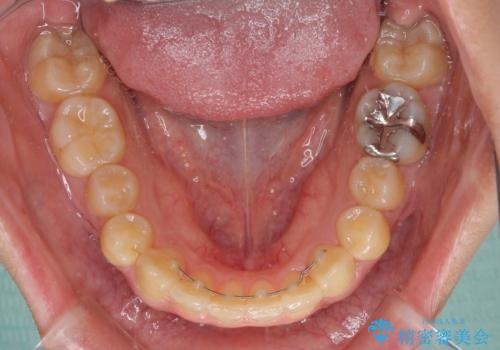

八重歯の抜歯矯正 補助装置を用いたインビザライン矯正

装着時間をしっかりと守ってくださったので、予定通りの期間で終了することができました。

- 矯正治療後の保定が不十分だと後戻り(元の位置に戻ろうとする動き)をします